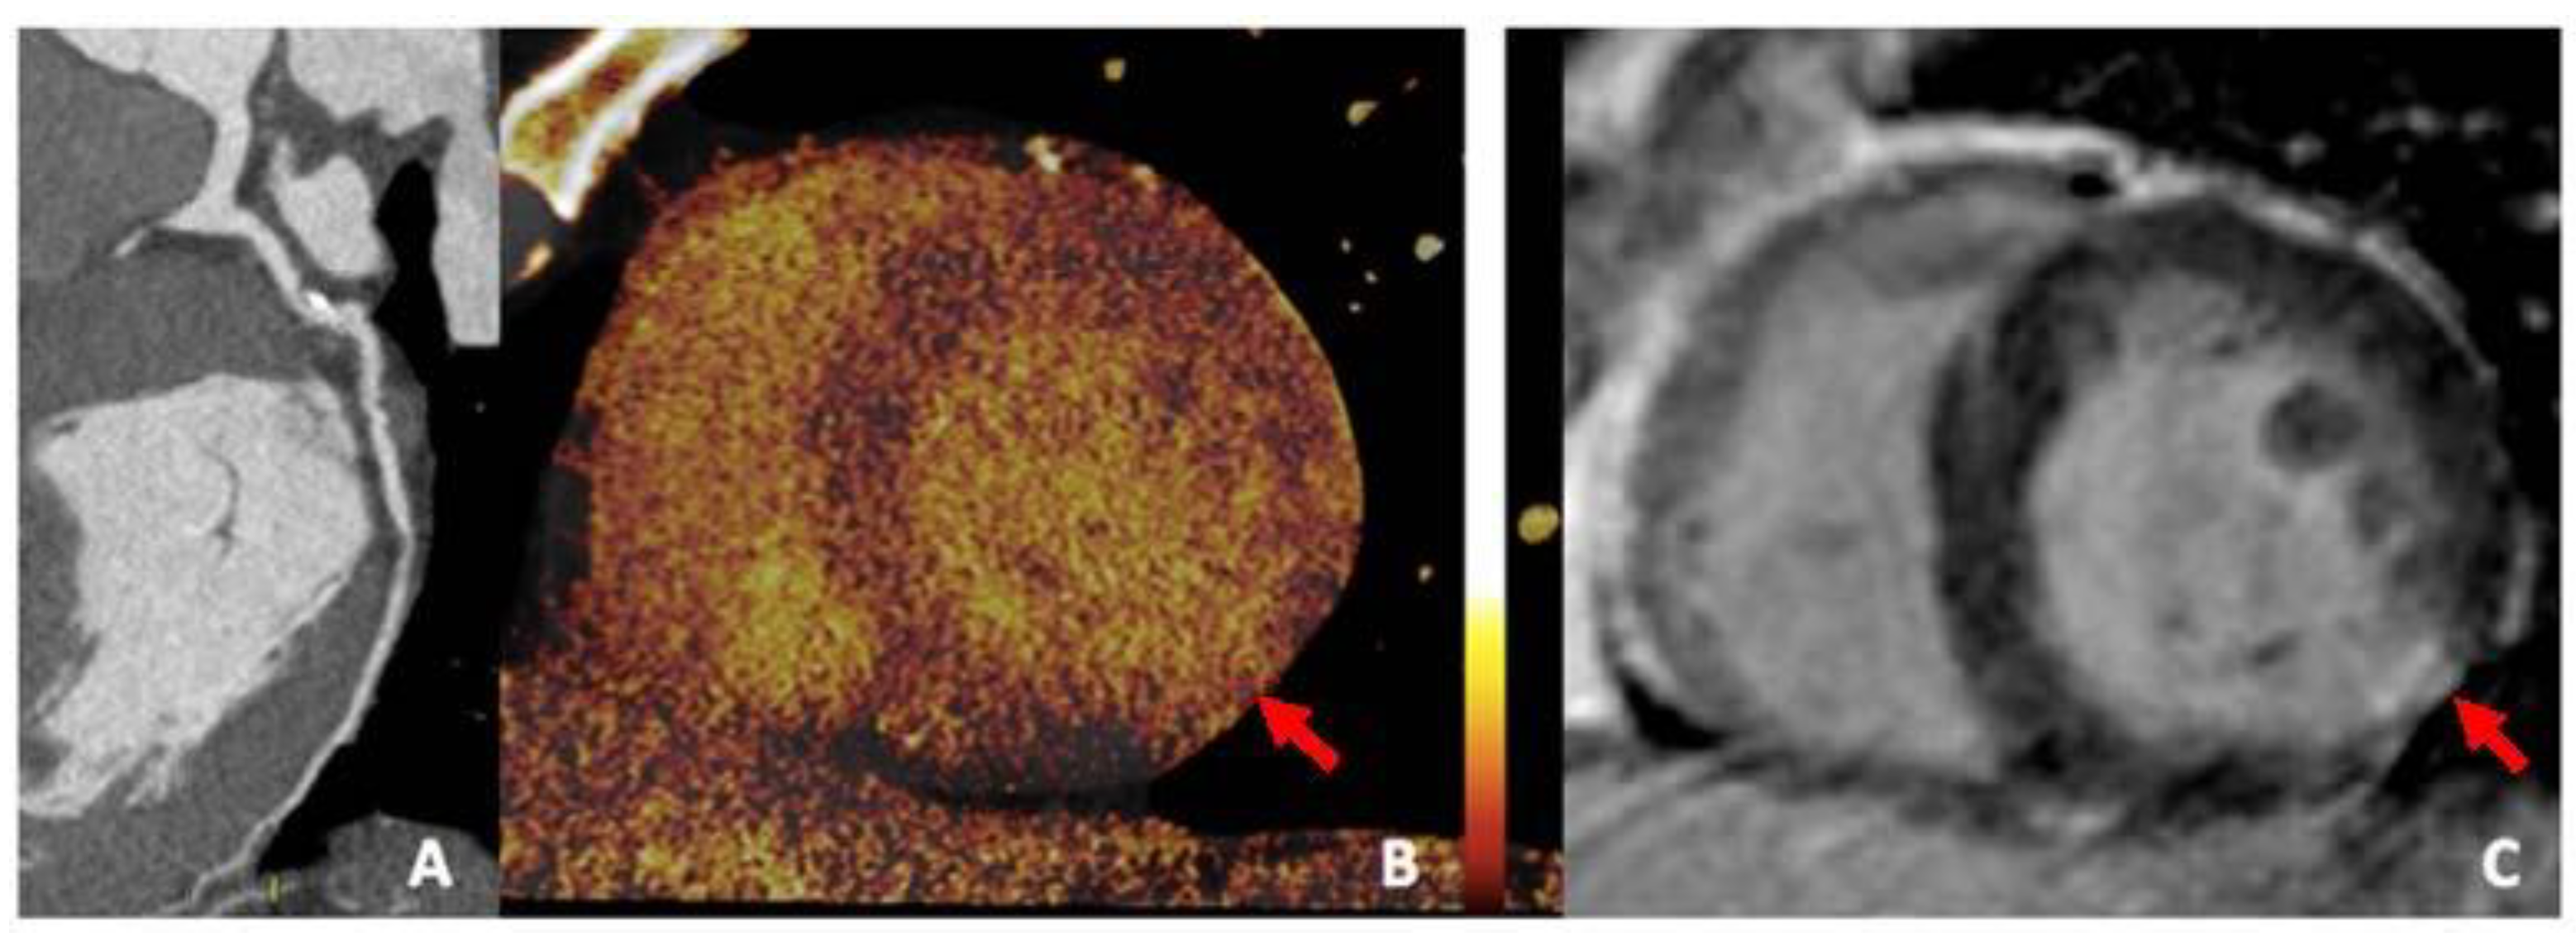

3.4. Iodine Perfusion Maps

3.6. Extracellular Volume (ECV)

- Jin, K.N.; De Cecco, C.N.; Caruso, D.; Tesche, C.; Spandorfer, A.; Varga-Szemes, A.; Schoepf, U.J. Myocardial perfusion imaging with dual energy CT. Eur. J. Radiol. 2016, 85, 1914–1921. [Google Scholar]

- Delgado Sánchez-Gracián, C.; Oca Pernas, R.; Trinidad López, C.; Santos Armentia, E.; Vaamonde Liste, A.; Vázquez Caamaño, M.; Tardáguila de la Fuente, G. Quantitative myocardial perfusion with stress dual-energy CT: Iodine concentration differences between normal and ischemic or necrotic myocardium. Initial experience. Eur. Radiol. 2016, 26, 3199–3207. [Google Scholar]

- Lee, H.-J.; Im, D.J.; Youn, J.-C.; Chang, S.; Suh, Y.J.; Hong, Y.J.; Kim, Y.J.; Hur, J.; Choi, B.W. Myocardial Extracellular Volume Fraction with Dual-Energy Equilibrium Contrast-enhanced Cardiac CT in Nonischemic Cardiomyopathy: A Prospective Comparison with Cardiac MR Imaging. Radiology 2016, 280, 49–57. [Google Scholar] [CrossRef]

- Ohta, Y.; Kishimoto, J.; Kitao, S.; Yunaga, H.; Mukai-Yatagai, N.; Fujii, S.; Yamamoto, K.; Fukuda, T.; Ogawa, T. Investigation of myocardial extracellular volume fraction in heart failure patients using iodine map with rapid-kV switching dual-energy CT: Segmental comparison with MRI T1 mapping. J. Cardiovasc. Comput. Tomogr. 2020, 14, 349–355. [Google Scholar] [CrossRef]